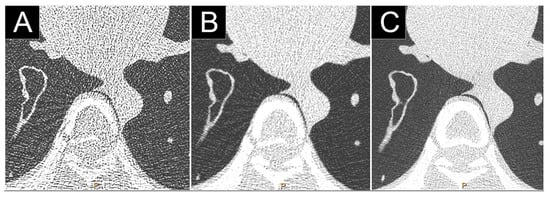

- Do, T.D.; Sawall, S.; Heinze, S.; Reiner, T.; Ziener, C.H.; Stiller, W.; Schlemmer, H.P.; Kachelrieß, M.; Kauczor, H.U.; Skornitzke, S. A semi-automated quantitative comparison of metal artifact reduction in photon-counting computed tomography by energy-selective thresholding. Sci. Rep. 2020, 10, 21099. [Google Scholar] [CrossRef]